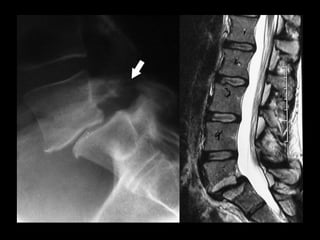

FUSION FOR LOWBACK PAIN Interbody fusion

remove the disc Interbody fusion • removethe pain source • stop the movement FUSION FOR LOW BACK PAIN